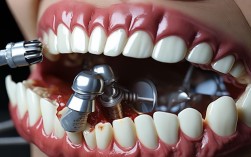

🦷 2. 口腔局部条件

- 牙槽骨状况: 种植牙需要足够的骨量来支撑种植体,70岁老人常因长期缺牙、牙周病等导致牙槽骨吸收严重,可能需要进行骨增量手术(植骨),这增加了手术复杂性和风险。